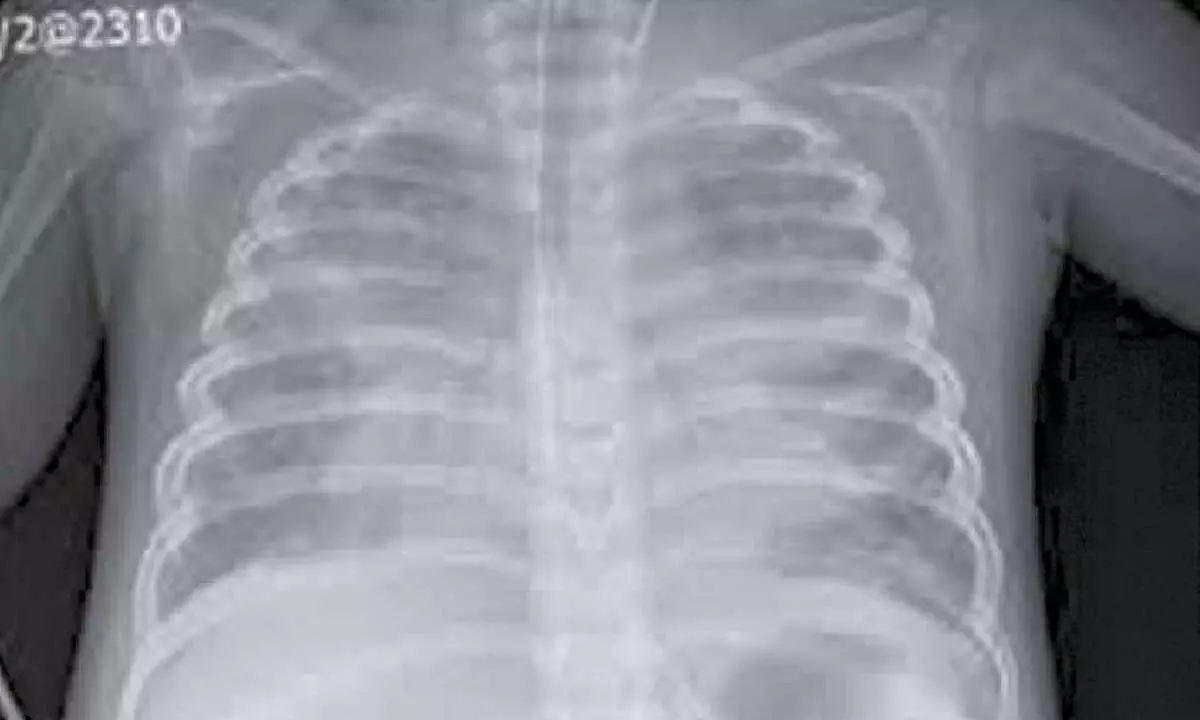

Bengaluru: In a complex case within paediatric critical care, physicians at Rainbow Children’s Hospital, Bannerghatta Road, have treated successfully a three-year-old boy from Bengaluru who suffered from tuberous sclerosis, refractory seizures, alongside severe Paediatric Acute Respiratory Distress Syndrome (PARDS). This was one of the most challenging, high-risk cases, where the child’s rare genetic condition demanded specialist, aggressive care and seamless teamwork, testing clinical skill, judgement, and coordination to steer him through a perilous course to recovery. In India, the prevalence of tuberous sclerosis complex is about 1 in a lakh individual, and PARDS affects approximately 6% of all patients requiring mechanical ventilation in Paediatric Intensive Care Unit (PICU). It is also important to highlight that in severe cases of PARDS, the case mortality rate is 32% which is significant in highlighting the importance of survival in this specific case.

The 3 year-old boy came to the hospital earlier this year and presented with fever, tachypnea, and profound dyspnea. Due to the acute type 1 respiratory failure, he was put on mechanical ventilation due to PARDS. His condition was further complicated by difficult-to-control seizures requiring high doses of repeated anti-epileptic drugs. Without urgent and aggressive intervention, the risk to life was extremely high.